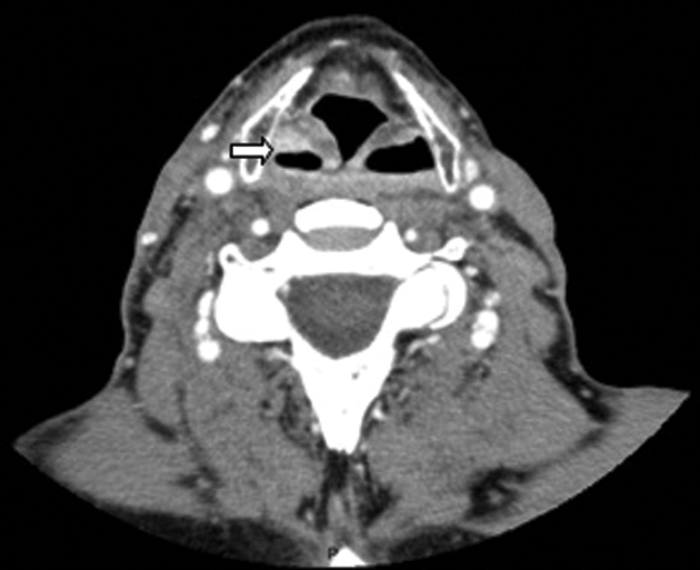

A 47-year-old male presented with right-sided otalgia. Otoscopy was normal. Five years previously he had chemoradiotherapy treatment for squamous cell carcinoma of the right hypopharynx. There was mucosal irregularity of the right pyriform sinus. CT demonstrated a small recurrence in the pyriform fossa (Figure 10). CT is the imaging method of choice for the larynx and hypopharynx. MRI is useful in assessment of thyroid cartilage, however it is sensitive to respiratory motion.

Figure 10: Contrast enhanced soft tissue axial CT demonstrating a small enhancing

squamous cell carcinoma recurrence within the right pyriform fossa (white arrow).